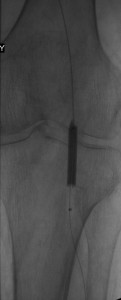

In this patient, a 67 year-old woman with long-standing diabetes, there was a plantar ulcer of her anterior left forefoot that resisted healing despite many noninvasive treatments. Her podiatrist referred her to me and her sonographic and angiographic investigations revealed multiple significant stenoses in her distal left superficial femoral artery (LSFA), left popliteal artery, and her anterior tibial artery. Her posterior tibial artery was occluded and her chief path of blood flow to the left foot was her left peroneal artery. Her arterial paths above the distal left SFA were open and she had stage 3 chronic renal insufficiency. Faced with the dilemma of continuing foot infection and potential limb loss and worsening renal insufficiency following exposure to radiocontrast, she put off endovascular revascularization of the arterial narrowings for sometime, finally caving to pressures from her son.

After instituting strategies to minimize contrast-induced nephropathy, I employed atherectomy of the distal LSFA and popliteal stenoses and angioplasty of the multifocal stenoses of her anterior tibial artery down to the dorsalis pedis artery to restore reasonable flow to her foot that helped the ulcer heal.

Images in the top panel illustrate her disease before the interventions, those in the middle panel illustrate some intraprocedural steps (balloon angioplasty), while those in the bottom panel illustrate improved blood flow to the foot following treatment.